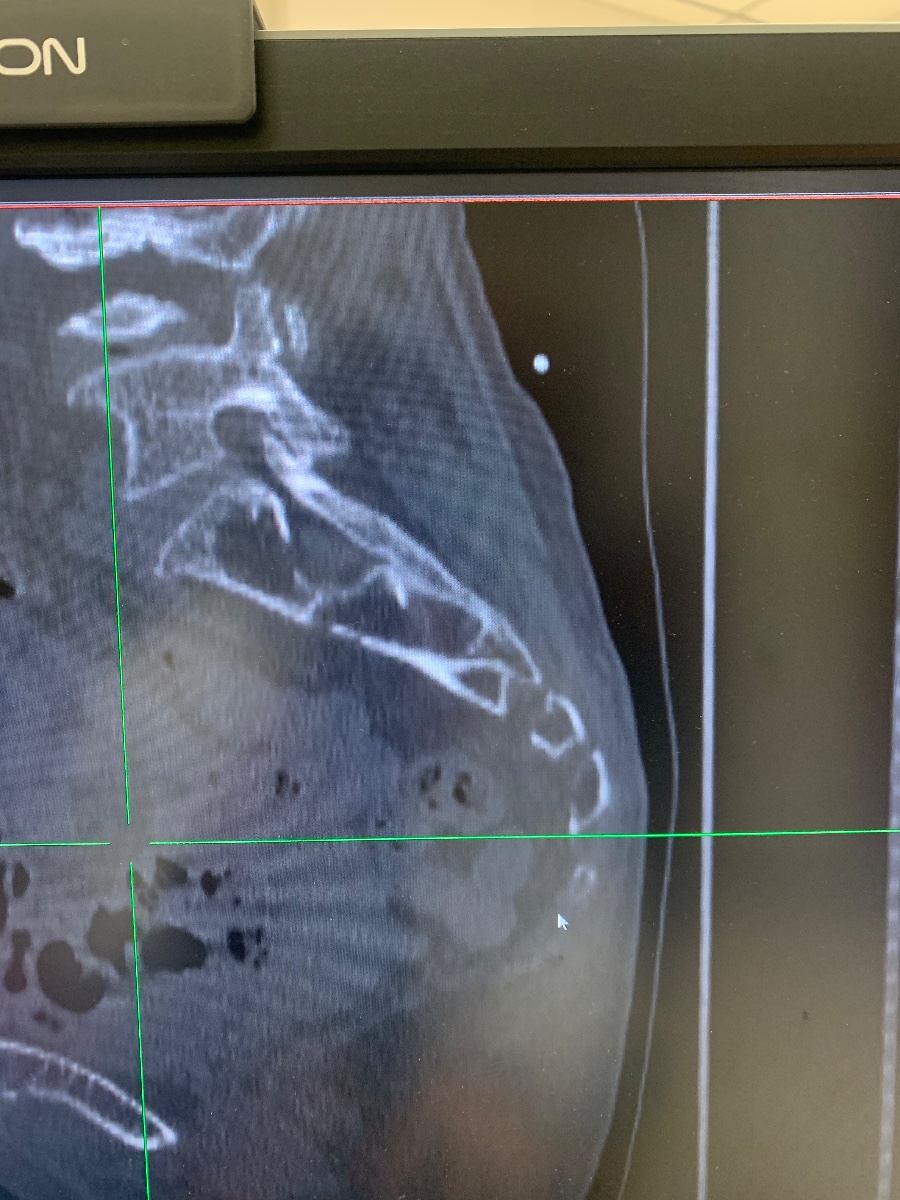

【病例讨论】左侧骶骨、髂骨病变

患者女,70岁,四年前因骶髂关节痛,于三级医院摄X片,提示骶髂关节炎,CT检查又考虑结核,但实验室等检查,未查到结核菌,但仍进行了抗结核治疗。未见旧片,今患者左侧乏力,左侧倾倒就诊。我院CT片如下图:

浆细胞瘤。

从部位来看,我觉得考虑骨巨细胞瘤,可以跨关节。鉴别脊索瘤和低度恶性软骨肉瘤。上面老师考虑浆细胞瘤,是不是有残存骨脊,有点像“微脑征”,但是我觉得浆细胞瘤是不是骨质破坏密度还要低一些?期待病理答案